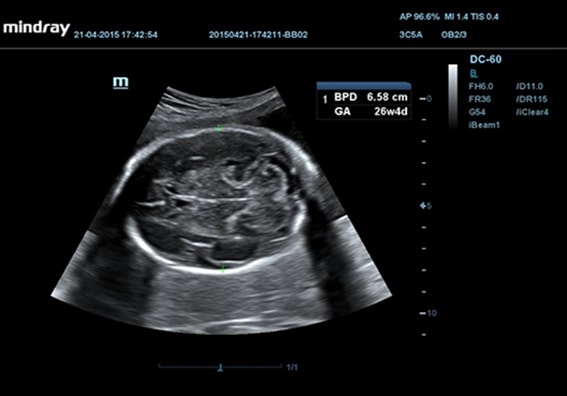

• Smart OB™ - программа автоматического расчета с возможностью ручного редактирования основных акушерских показателей: БПР, ДБ, ОГ, ЛЗР, с использованием алгоритмов автоматического оконтуривания и распознавания границ органов

• Конвексный датчик Mindray 3C5A